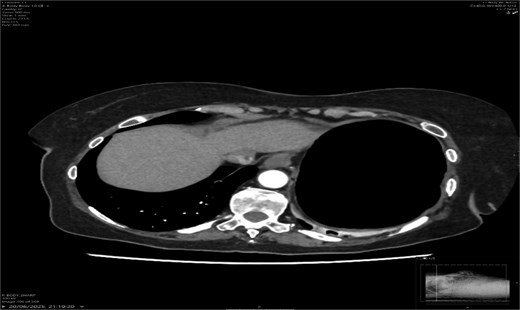

A contrast-enhanced CT scan of the abdomen demonstrated a whirl sign at the mesenteric root (Figs 1 and 2), dilated transverse colon with a transition point at the splenic flexure (Fig. 3), and no evidence of ischemia or perforation (Fig. 4). These findings were consistent with TCV.

Radiology plays a crucial role; plain abdominal radiographs may show nonspecific distension but rarely establish the diagnosis. A CT scan is the gold standard [8], with the whirl sign, transition point, and proximal dilatation being diagnostic. CT also assesses complications such as ischemia and perforation, which carry high mortality [9].